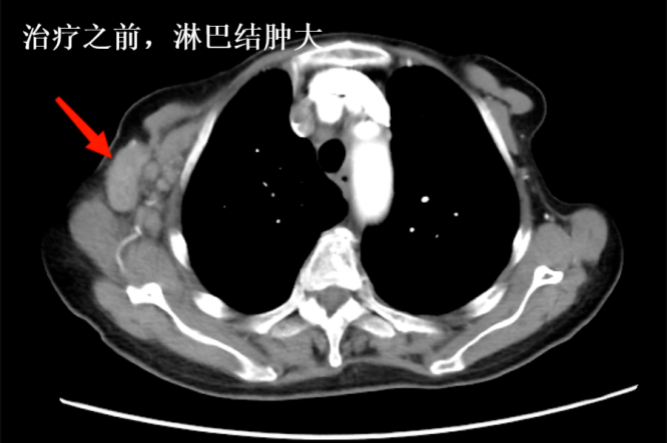

王奶奶在治療后,并沒有出現(xiàn)任何不適的癥狀。更令人驚喜的是,當(dāng)她入院復(fù)查時(shí),發(fā)現(xiàn)腫瘤竟然比之前縮小了。這個(gè)顯著的療效讓王奶奶和家屬對(duì)抗腫瘤的信心一下子足了起來。

再一次復(fù)查時(shí),她的身體狀況明顯好轉(zhuǎn),體內(nèi)的腫瘤竟然再次大幅度縮小,精神面貌也煥然一新,胸悶和全身水腫的癥狀完全消失。如今,她不僅能夠完全自理生活,生活質(zhì)量與常人無(wú)異。